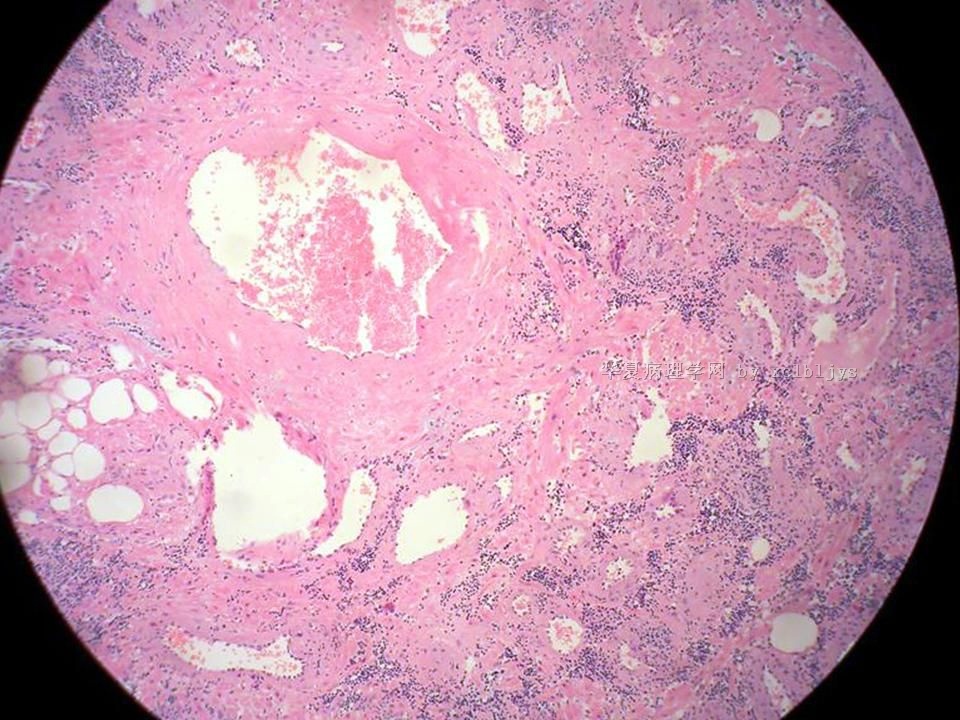

| 以下是引用xclbljys在2010-12-22 17:20:00的发言: 本例我们科室医生有两种意见:一种是炎性假瘤;第二种意见是炎性假瘤伴局限性Wegener肉芽肿。 依据是眼眶内肿块含有大量的动脉内膜炎改变,浸润的炎细胞有淋巴细胞、浆细胞、嗜中性粒细胞和嗜酸细胞等,如图16所示,炎细胞已经浸润动脉壁全层,应符合坏死性小动脉炎,但尚不能确定动脉壁弹力纤维层的破坏。 请各位老师点评! Wegener肉芽肿多发生在上呼吸道、肺、肾脏和皮肤等器官与组织。坏死性血管炎需证实有纤维素样坏死。小动脉炎多在皮肤病变比较明显。本例的小动脉炎或许是炎症引起的继发性改变。需要完善病史,查血免疫指标,看有没有系统性疾病。如果没有系统性疾病,还是考虑慢性炎症继发小血管炎。

血管炎是正常营养/供给血管的炎症性病变,而不是增生血管的炎症。血管炎往往有明显的临床相应症状,如皮疹。典型的Wegerner肉芽肿病有三联症(上呼吸道、肺、肾脏病变)。血管炎不仅是有炎症细胞,同时有血管壁的变性、坏死(纤维素样), 内皮细胞的变质和增生,炎症细胞浸润(包括中性粒细胞、淋巴细胞、组织细胞、嗜酸性细胞、巨细胞等)。不同类型的血管炎累及的血管大小、炎症细胞的类型、有无肉芽肿改变都不相同。血管炎的病因可以是过敏、自身免疫、胶原性疾病、感染等多种因素。